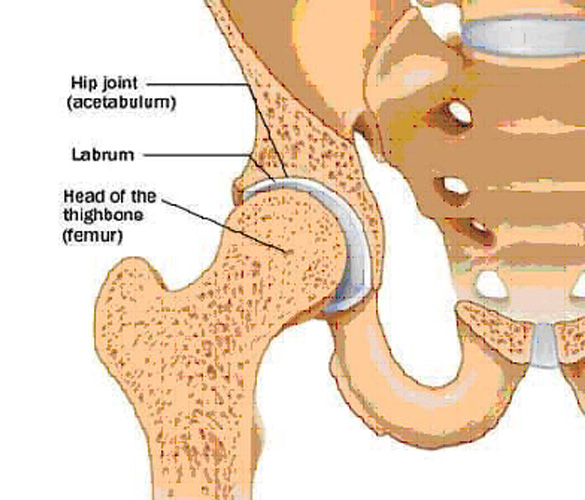

What is the difference between a torn shoulder cartilage and a hip joint?

The shoulder has a ball and socket joint which is similar to the hip joint. However, as compared to the hip joint, the shoulder joint is shallow and unstable.

What is the labrum in the shoulder?

To prevent the dislocation of the bones in the shoulder joint, there is a layer of rotator cuff muscles (or the shoulder muscles), called labrum to provide extra support to the shoulder.